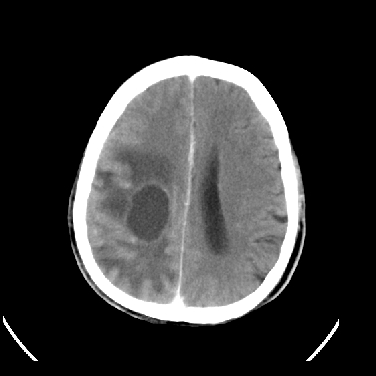

男,45岁,左侧肢体乏力1周。ex:胸片示:两肺团块状、斑片状密度增高影,其内可见小空洞。支纤镜、经皮肺穿示:干酪样物。

结合病史考虑结核性脑炎脑膜炎,伴脑脓肿形成

考虑右侧顶叶脑脓肿形成。

同意“考虑结核性脑炎脑膜炎,伴脑脓肿形成”的意见,不轻易怀疑肿瘤。

考虑右侧顶叶脑脓肿形成

考虑结核性脑炎脑膜炎,伴脑脓肿形成。

右侧顶叶脑脓肿!支持!

考虑右侧顶叶脑脓肿(结核性?)。

结核性脑脓肿可能大

结合病史考虑结核性脑炎脑膜炎,伴脑脓肿形成,囊变转移瘤不除外